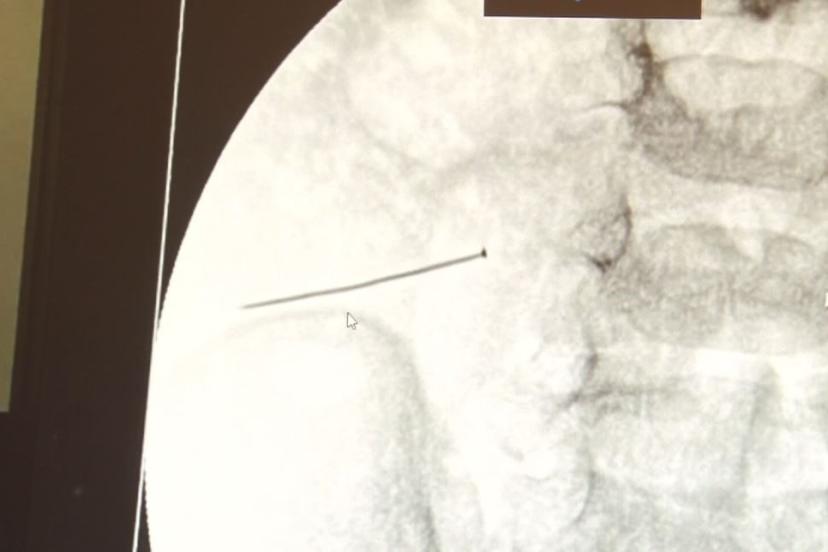

Öte yandan, yaklaşık 3 santimlik toplu iğne filme yansıyan görüntüsüyle gözler önüne serildi.